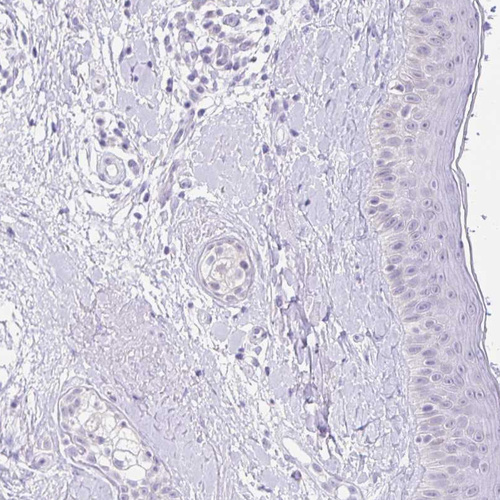

Immunohistochemistry analysis in human testis and skin tissues using HPA034604 antibody. Corresponding FATE1 RNA-seq data are presented for the same tissues.